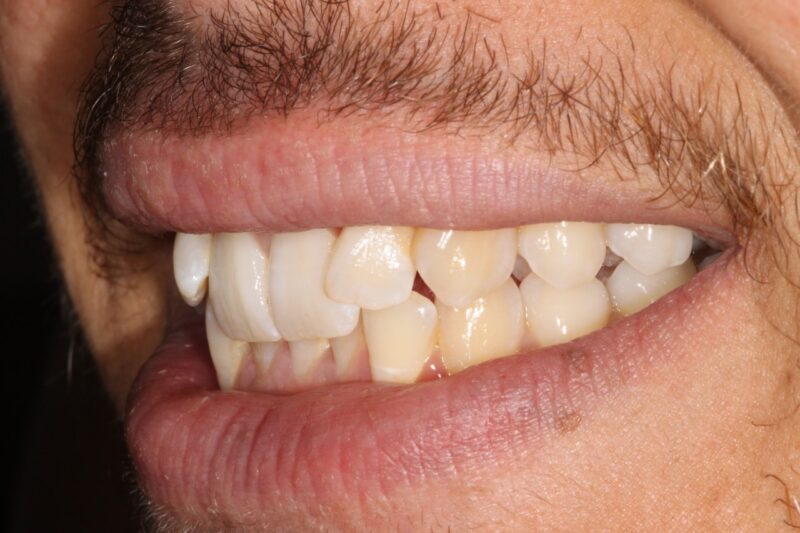

Invisalign Gallery Case 21

This patient was treated with upper and lower invisalign followed by reshaping his front teeth with composites